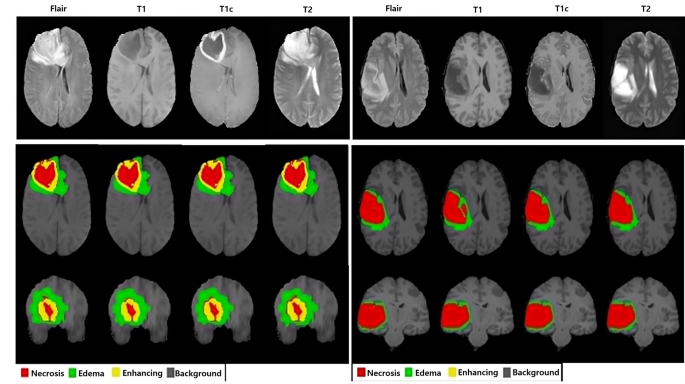

To surmount these challenges, we propose a Multi-Modal Multi-Scale Contextual Aggregation with Attention Fusion (MM-MSCA-AF) model for brain tumor segmentation. The proposed model integrates multi-modal MRI inputs to capture complementary tissue contrasts and employs Multi-Scale Contextual Aggregation (MSCA) to learn both global and fine-grained spatial features. A gated attention fusion (GAF) process is suggested to selectively enhance tumor-specific features and suppress noise, improving segmentation performance in necrotic, enhancing, and edema regions. The proposed framework is evaluated on the BRATS 2020 dataset, as illustrated in Figure 1, and achieves a Dice score of 0.8158 for necrotic tumor regions and 0.8589 overall, which is better than state-of-the-art models.

An encoder–decoder design is used by the MMSCA-AF paradigm for effectively segmenting brain tumors from multi-modal MRI components, such as T1, T2, FLAIR, and T1-CE. First, it extracts hierarchical features from the original dataset to obtain crucial structural details. Second, it enhances the precision of tumor boundary identification by combining contextual data at multiple spatial scales. Third, redundant information is suppressed, and feature visualizations are refined through the use of attention mechanisms. Ultimately, each pixel is classified into one of four tumor classes by the decoder, which generates high-resolution segmentation maps. Figure 1 illustrates the broader concept, which combines attention fusion and multi-scale feature extraction. Figure 2 presents the MMSCA-AF model representation, including multi-modal input processing, MCA, GAF, and the final segmentation output. This architecture is designed to capture both global and fine-grained tumor features for precise segmentation. For clarity, Fig. 3 provides the MMSCA-AF network legend, which explains the role of each model component.

The proposed MM-MSCA-AF model is evaluated on the Brain Tumor Segmentation (BRATS 2020) dataset, a widely used benchmark for brain tumor segmentation tasks32. The dataset consists of multi-modal MRI scans from 369 patients, with four MRI sequences available for each subject and is given by T1-weighted (T1) scan that highlights normal brain structures, T1 contrast-enhanced (T1-CE) scan that enhances tumor boundaries, T2-weighted (T2) scan that shows fluid accumulation around the tumor, and Fluid-Attenuated Inversion Recovery (FLAIR) scan that detects edema and tumor infiltration. Each scan is manually annotated by expert radiologists into four classes, e.g., Non-tumor regions, Necrotic tumor core, Enhancing tumor, Edema. The dataset is split into \(70\%\) training, \(20\%\) validation, and \(10\%\) testing to ensure model generalization across unseen cases.